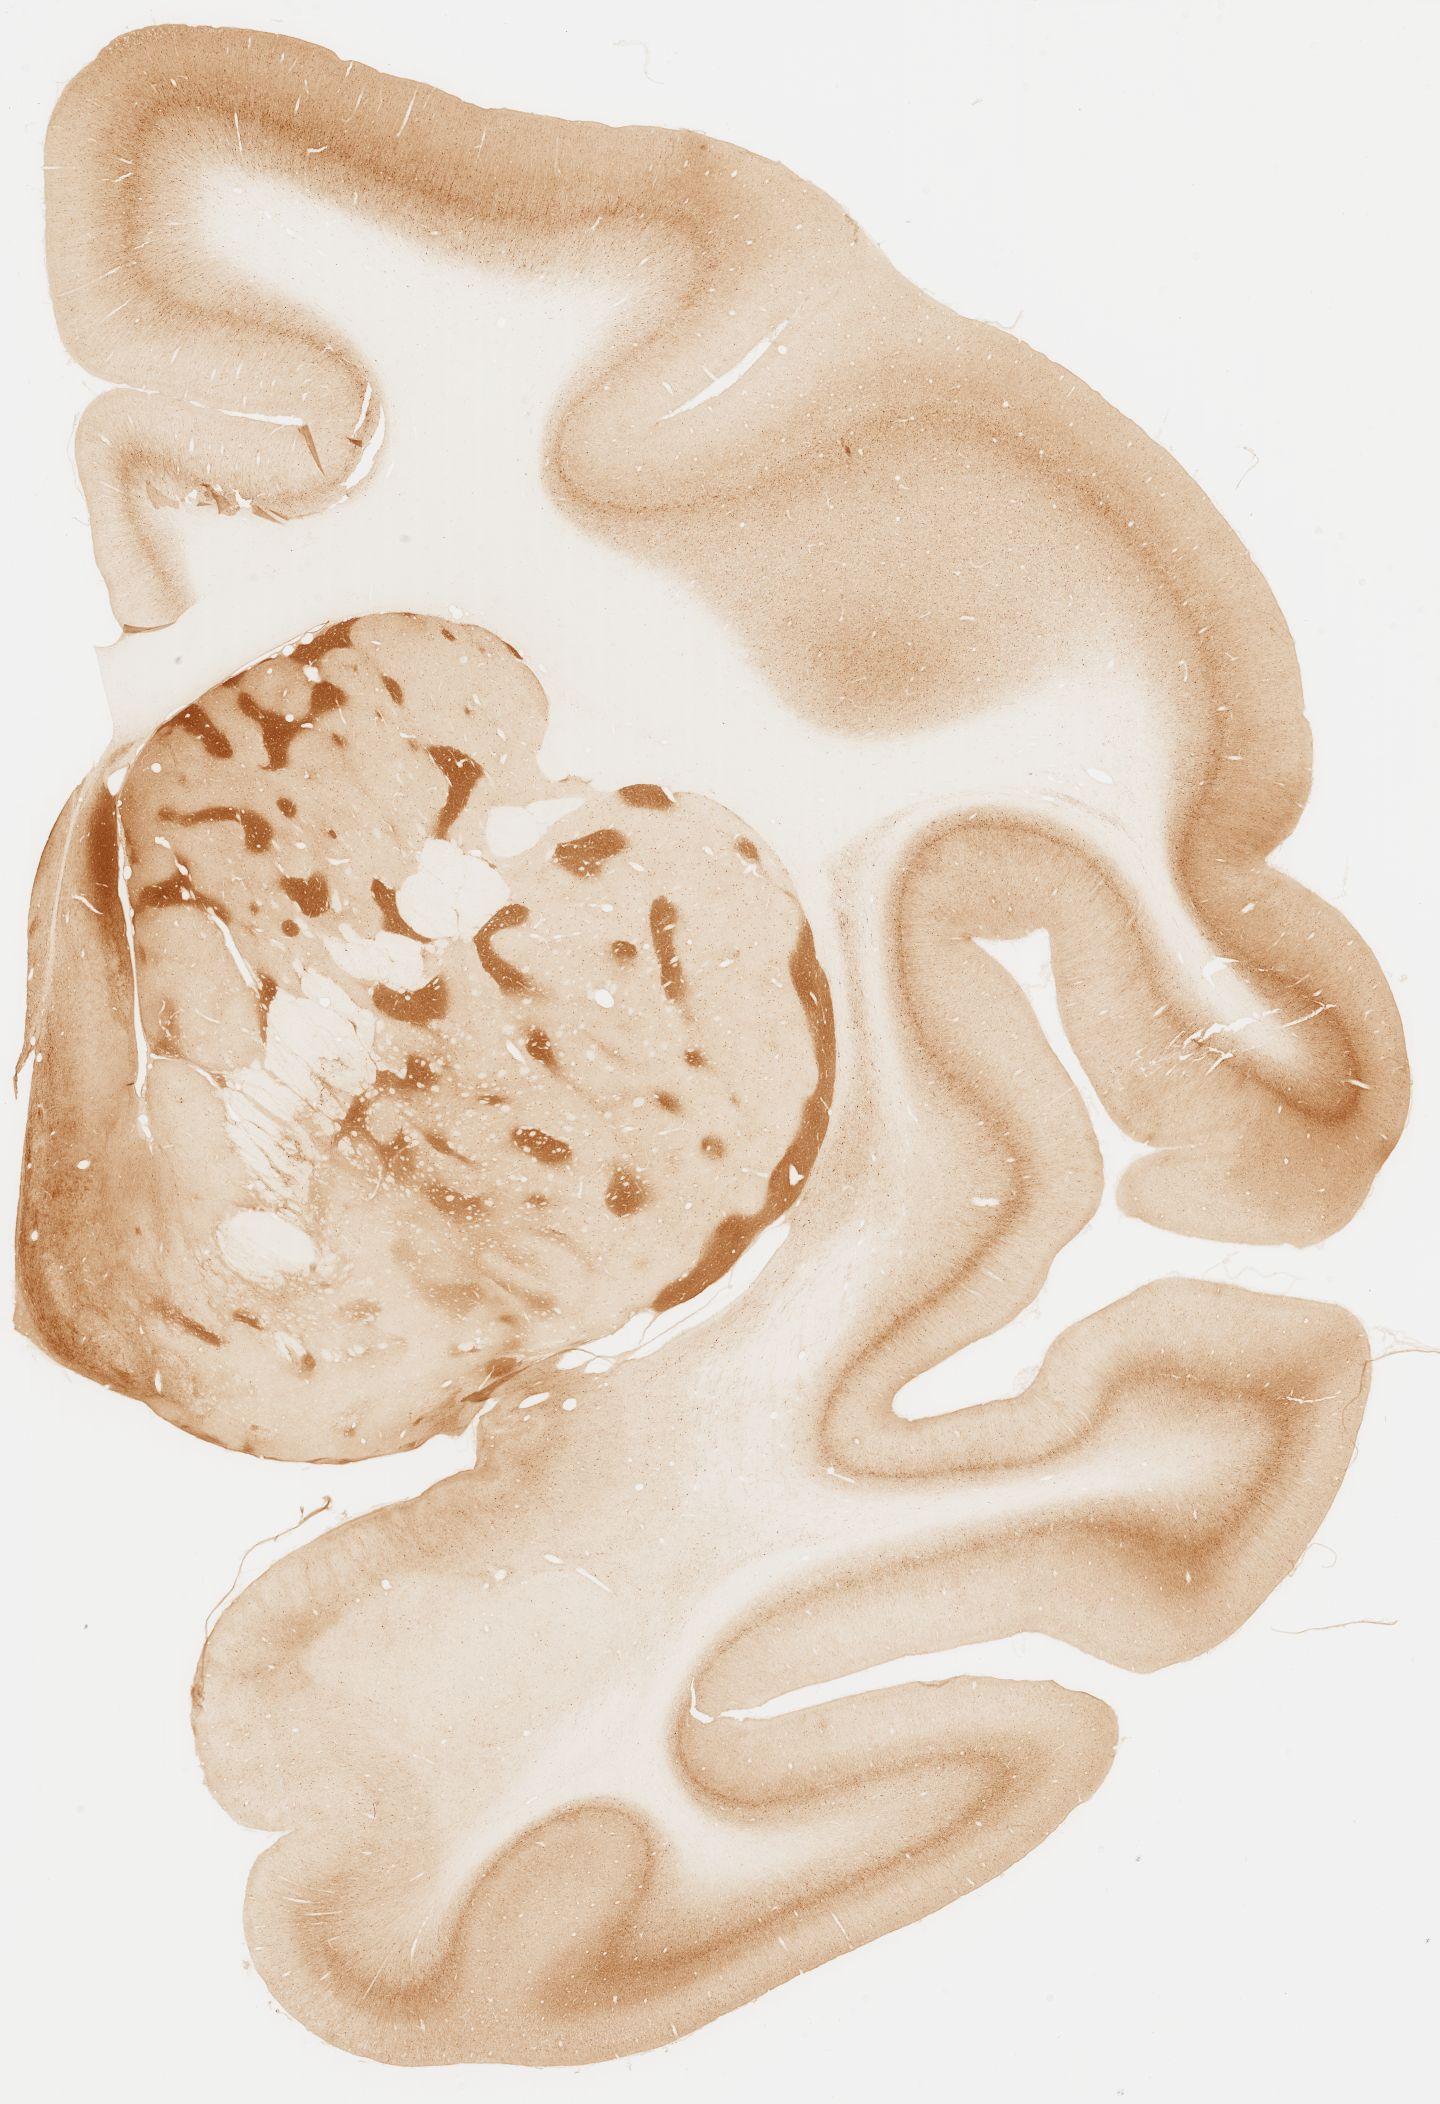

Datasets -> Macaca Fascicularis -> KChIP1, (Potassium Voltage-Gated Channel-Interacting Protein 1), coronal, immuno, Whole-Brain, adult

[ Metadata ]   ·   Source: Edward G. Jones

Displaying Sections 41 thru 80 of 92 Sections for this Dataset